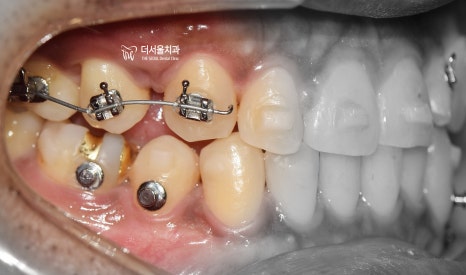

사용 된 장치로는

철사장치 및 인비절라인 인데

처음에는, 인비절라인 만 했었으나

환자께서.. 장치를 잘 끼지 않으셔서

치아 이동이 원활하게 되지 않았었죠.

그래서, 중간에 철사 장치로 발치 공간을

닫으면서 불규칙했던 치열을 바로 잡았습니다.